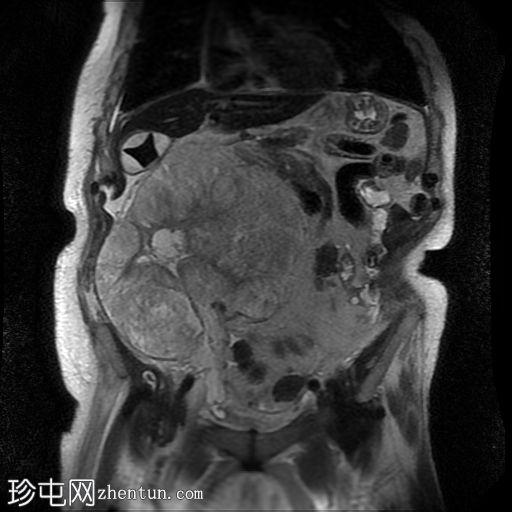

冠状动脉和主动脉瓣膜钙化明显。广泛的腹部动脉粥样硬化。胆结石。双肾萎缩。左髂窝移植肾形态大致正常。

右髂窝移植肾边界不清,呈低密度,周围环绕着一个大的分叶状复杂囊性肿块。